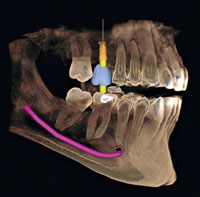

Leveraging AI for Diagnostic Excellence

Wednesday, June 5, 2024

The newest advancements in diagnostic imaging incorporate assisted intelligence (AI). Software can now help dentists more precisely and accurately identify areas of concern, trace the mandibular nerve, accurately plan dental implants, organize all images into a single template, and much more.